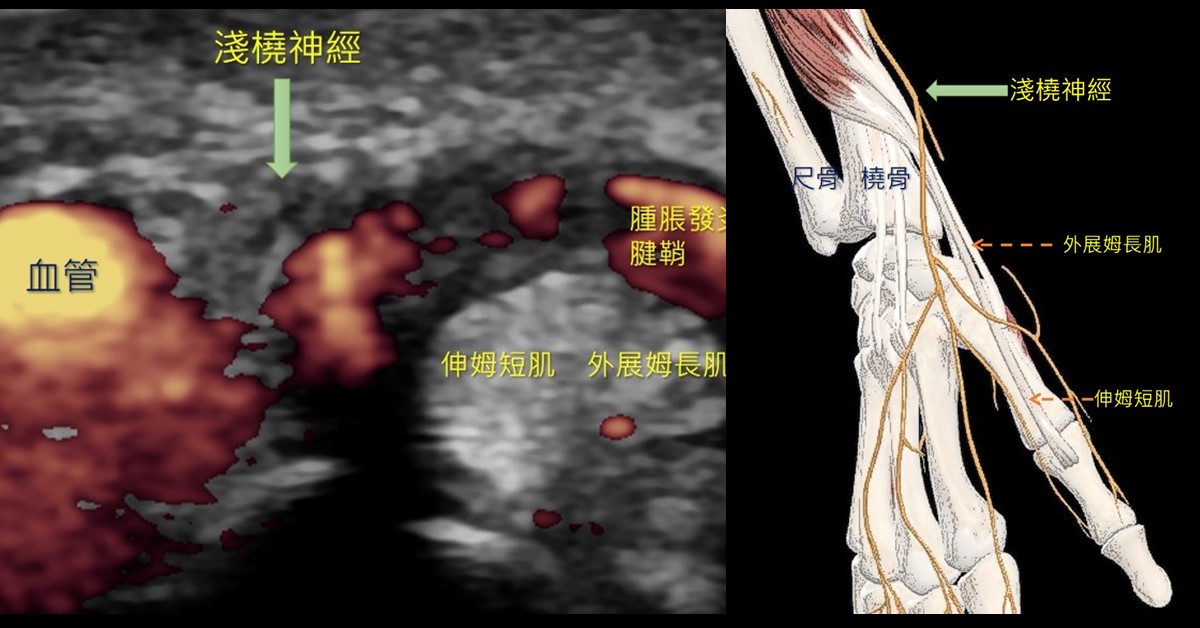

理學檢查發現前臂輕微水腫,手腕伸展角度些微受限,高解析度超音波檢查顯示外展姆長肌和伸姆短肌腱鞘腫脹,兩個肌腱旁邊的淺橈神經有腫脹的現象(圖一左),診斷為淺橈神經夾擠症與腱鞘炎。醫師執行超音波導引神經解套注射,並安排徒手治療來逐漸鬆動沾黏的組織,減少周邊水腫、增加手腕活動角度,這些不適感就有了明顯的改善。

淺橈神經夾擠症以手背橈側遠端三指半區域的麻刺感為主,壓迫位置好發於腕關節與手腕近端約4公分處,這些地方可以找到明顯壓痛點且在輕輕敲擊下,可以讓不舒服的症狀再現。淺橈神經會跨過外展姆長肌與伸姆短肌肌腱的表層 (圖一右),下行支配第一到第三指背側的感覺,所以會有上述症狀。